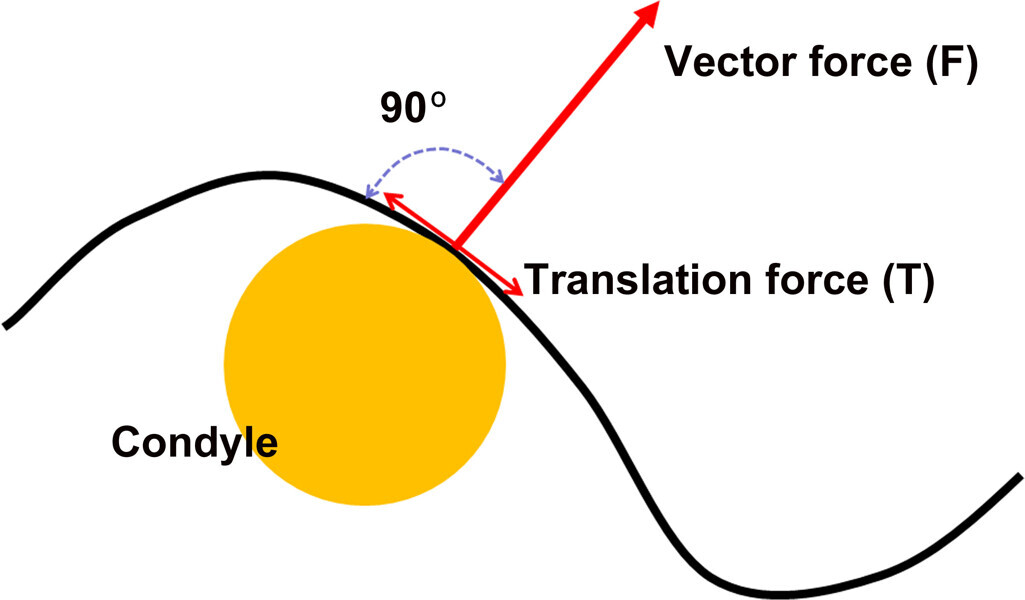

Fig. 9: The condyle position is based on the vector of force of the elevator muscles—perpendicular to the contour of the eminence.